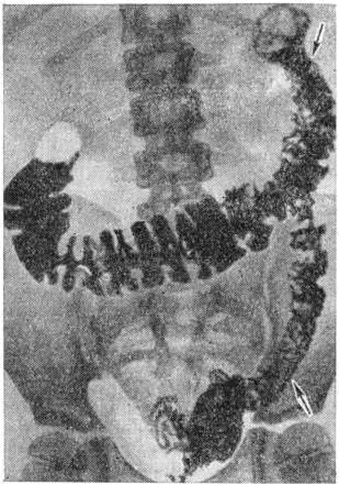

Рис. 2.

Рентгенограмма поперечной ободочной кишки при болезни Крона: гаустрация кишки отсутствует, контуры кишки неровные, зубчатые со спикулоподобными выступами.